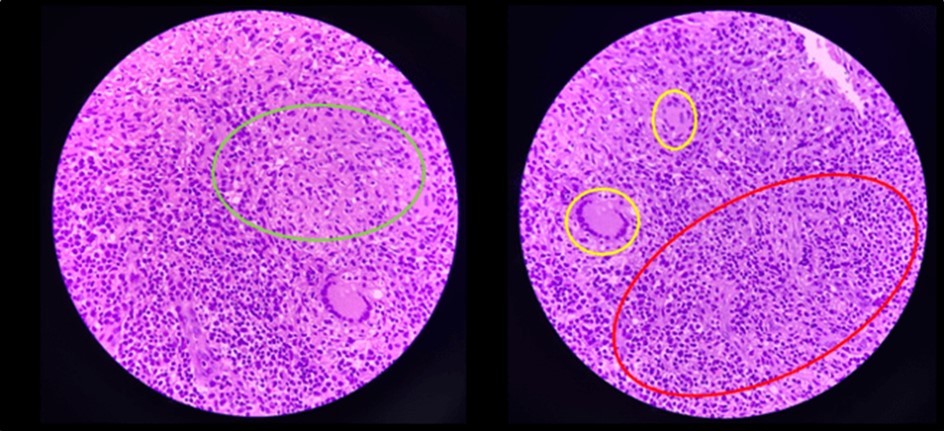

Biopsy showed chronic granulomatous inflammation with caseation necrosis and Langhan’s type giant cells consistent with tuberculous etiology (Figure 6, and Figure 7). TB PCR detected Mycobacterium tuberculosis, Rifampicin (MTB, RIF) resistance indeterminate. Category I Anti-TB treatment for six months was started and the service planned to repeat both colonoscopy and CT-scan after the initial round of anti-TB treatment. Currently, the patient is able to work with no abdominal pain and was able to tolerate her anti-TB drug regimen

Figure 7.Pathologic slide in the high power field. Inside the green circle is the epitheloid histiocytes. The yellow circles are the Langhan’s type multinucleated gian cells. And inside the red circle is the lymphocytic infiltrates. Which is suggestive of tuberculous etiology.

Pathologic slide in the high power field. Inside the green circle is the epitheloid histiocytes. The yellow circles are the Langhan’s type multinucleated gian cells. And inside the red circle is the                        lymphocytic infiltrates. Which is suggestive of tuberculous etiology.